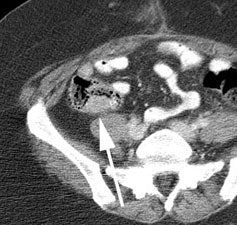

Recurrent colorectal cancer: The patient shown below had a history of colon cancer and a rising CEA level. FDG PET exam revealed a site of tracer uptake in the mesentery (black arrows) which corresponded to an enlarged lymph node seen retrospectively on CT scan (white arrow). |

|